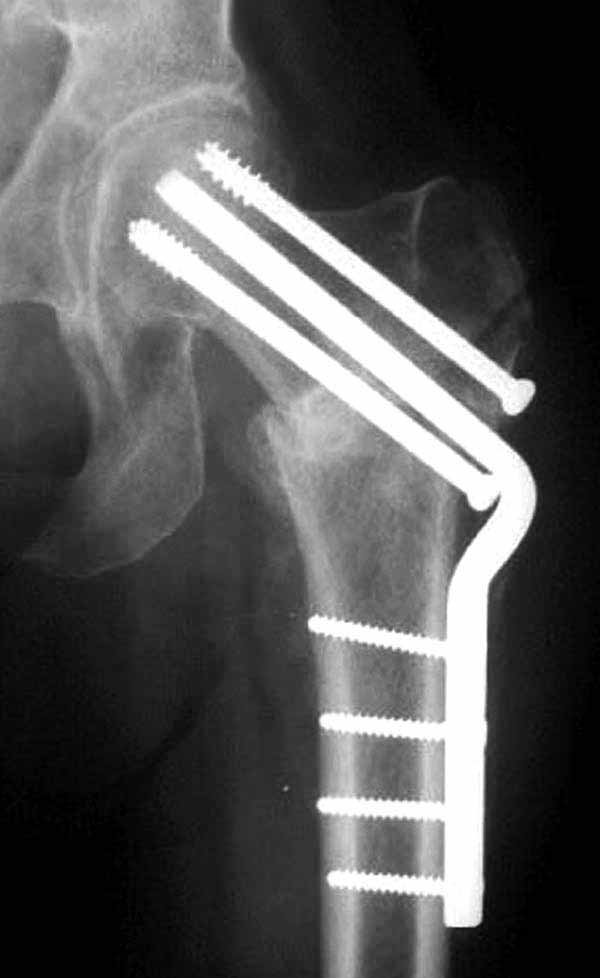

Пациентка Ш. 76 лет, 11 дней назад прооперирована по поводу вколоченного субкапитального перелома шейки левой бедренной кости, 3-мя канюлированными винтами. Вчера пациентка упала в палате. И вот результат- подимплантатный подвертельный перелом левой бедренной кости. Уважаемые коллеги, пожалуйста посоветуйте какой метод дальнейшего лечения предпринять дальше.Соматически пациента повышенного питания, страдает варикозной болезнью нижних конечностей.Из предложенных вариантов коллег - целллокастовая укороченная кокситная повязка, скелетное вытяжение сроком на 40-45 суток - отпали сразу, так как необходимо активизация пациентки.На данный момент рассматриваем следующие варианта реостеосинтеза:(наличие технических возможностей) 1. Длинная Gamma 3 Stryker (с предварительной интраоперационной фиксацией головки спицами).2. Трохантерный штифт DePuy с 2-мя метафизарными винтами в проксимальном отделе, (также с интраоперационной фиксацией головки спицами. Очень настораживает стабильность фиксации с проксимальном отделе с связи с выборкой костной ткани ранее находящимися там канюлированными винтами. Сейчас пациентка находится на скелетном вытяжении, с дисциплинирующим грузом. Операция планируется после праздников. Заранее извиняемся за качество и неполное соответствие проекций на R-ммах (R-служба отдельная песня). При интраоперационном ЭОП-контроле винты в аксиальной проекции разнесены по шейке.

Перелом, как мне кажется, "чрезимплантный." Мы бы убрали два нижних винта, верхний не трогали (для ротационной стабильности в последующем)+ поставили-бы DHS. Направляющую спицу для шеечного винта вводите до удаления нижних и тогда потеря головкой девственности не будет иметь такого значения.

1. винты расположены не в лучшем положении:

два в нижней части шейки. Более стабильная структура как раз обратная: два шурупа в проксимальной части шейки , и не дальше центральной части головки, иначе есть риск пенетрации. дистальный винт мог бы быть выше уровня малого вертела. Его дистальное расположение описано с увеличенным риском послеоперационного перелома.

Согласен с Николаем, винты распоожены так, чтобы эту "мину" заложить. И два внизу, и не должны, даже если один он там, они входить ниже уровня малого вертела, это резко повышает риск подвертельного перелома. Что до остеосинтеза - учитывая 76 лет, более подходящей представляется большего диаметра винт в шейке, то есть гамма.

Работа Burstein AH and Wright TM: Fundamentals of Orthopaedic Biomechanics. Williams & Wilkins, Baltimore, pp. 160-169, 1994 доказывает, что шурупы, введенные на уровне малого вертела или ниже, приводят к осложнению. Введенные шурупы под 135 и больше градусов в 20% осложнились подвертельными переломами бедра.

У больных с ожирением и соматическими заболеваниями нежелательно открывать место перелома. Гвозди от DePuy с двумя шурупами рассчитаны для переломов бедра, и приходилось их применить для фиксации подвертельных переломов, но более адекватную фиксацию создает Gamma 3.